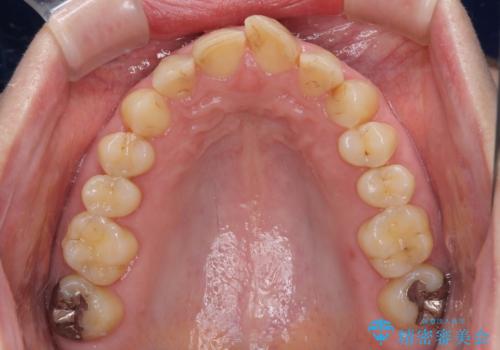

抜歯してからインプラント埋入までには時間がかかるため、その間に下顎左右臼歯の金属のブリッジをオールセラミックへ変えていくこととしました。

継ぎ接ぎだらけの上顎前歯もオールセラミッククラウンにて審美的に改善したいとのことでしたが、捻れが強くあるため、事前に矯正治療で歯列を整えてから、補綴治療を行うこととしました。

目立つ部分の銀歯や気になる変色歯をまとめてきれいに仕上げることができました。